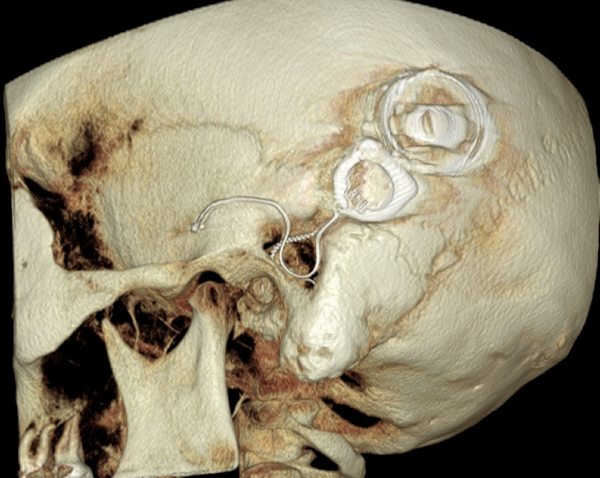

Both patients were imaged immediately with CBCT using SCANORA® 3Dx (Soredex, Tuusula, Finland). The field of view (FOV) was 140 x 165 mm and voxel size 0.2 mm. Imaging parameters were 90 kV, 8 mA, 4.00s. Standard 1 mm axial, coronal and sagittal reformations were made, as well as MIP and 3D reconstructions using OnDemand3D™ software (Cybermed, Seoul, South Korea).

CBCT proved to be optimal for imaging of these implants because of the superior bony delineation and nearly artefact free images. All four parts, i.e. the receiver stimulation part, extracochlear electrode implanted on the surface of the temporal bone, the extracochlear electrode plate and the intracochlear electrode array could be well imaged with CBCT.

On CBCT all four of the important parts of the implant were very well seen both on the axial slices and three dimensional surface reconstruction images. The implant is placed on magnetic plates, and the extracochlear part was seen in an abnormal separated position. The intracochlear electrode array showed no signs of separation in either of the cases. The intracochlear electrodes were well seen in both of the cases.

Figure 3: 3D reconstruction image of patient 1.